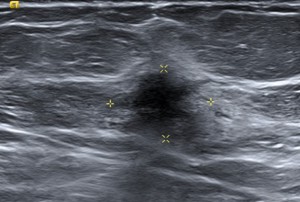

HALLAZGOS RADIOLÓGICOS